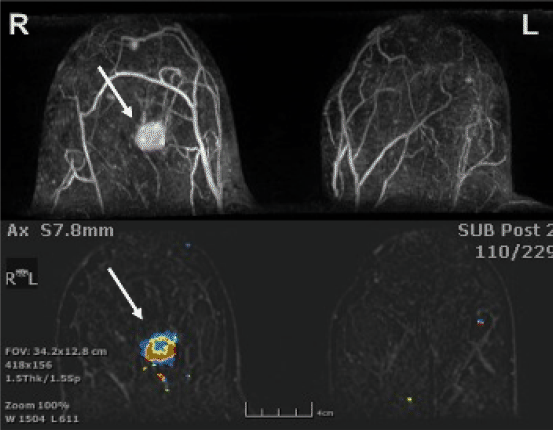

Figuur 5

MRI mammae na contrast, uitgevoerd omdat patiënte neoadjuvante chemotherapie zal ondergaan. Axiale coupes met hierin een pathologisch aankleurende irregulaire massa centraal in de rechtermamma (pijlen) met hypertrofische bloedvaten. Deze tumor was al bekend van mammografie en echografie. BI-RADS 6, PA-bewezen maligniteit.